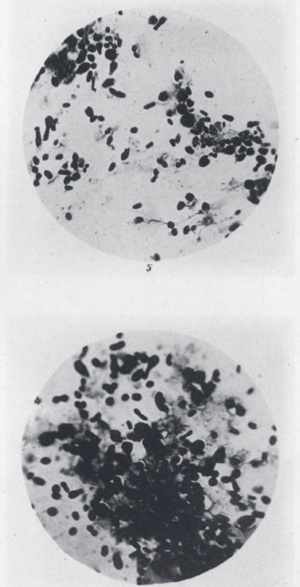

| A scanning electron micrograph showing a group of Yersinia pestis bacteria inside a flea. | |

Yersinia pestis looks like a safety pin when viewed under a microscope with special dyes. It grows best at temperatures between 28 °C and 30 °C (82–86 °F). However, it is very sensitive to sunlight and heat. If it is exposed to ultraviolet (UV) light or gets too hot (above 40 °C or 104 °F), it dies quickly.